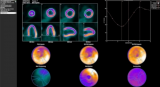

纽瑞特医疗完成68Ga-NRT6020注射液及177Lu-NRT6020注射液安全性和耐受性I期临床试验首例受试者入组

近日,由成都纽瑞特医疗科技股份有限公司(以下简称纽瑞特医疗)申办的一项评价68Ga-NRT6020注射液及177Lu-NRT6020注射液在FAP阳性晚期恶性实体瘤受试者中的安全性和耐受性的I期临床试验于复旦大学附属肿瘤医院(主要研究者:宋少莉教授、张剑教授)成功完成首例受试者给药,这标志着该项临床研究已从筹备阶段正式进入实质性实施阶段,也是68Ga-NRT6020注射液及177Lu-NRT6020注射液诊疗一体化开发过程中的一个重要里程碑。关于FAPFAP是具有细胞... 2025-12-05 核医学放射性药物核医药